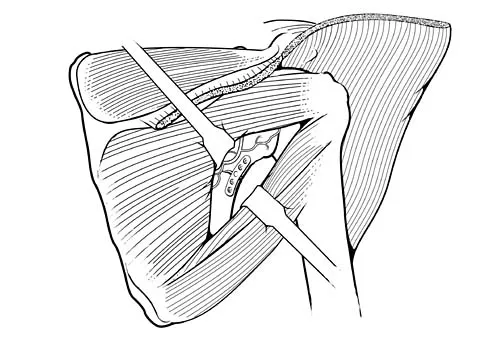

During treatment of rupture of the subscapularis tendon with associated biceps instability, treatment of the biceps tendon should include which of the following?

Explanation

With subscapularis tendon ruptures that have biceps tendon pathology, treatment with tenodesis or tenotomy has improved clinical results. Subluxation or dislocation of the biceps tendon is common with subscapularis rupture. Dislocation of the biceps can occur either beneath the tendon, within the tendon, or extra-articularly. In all cases, the restraints to medial translations of the biceps have been disrupted. Attempts at recentering the biceps have not been successful, and clinical results appear to be improved when tenodesis or tenotomy is employed in the treatment of the unstable biceps associated with subscapularis tears. Edwards TB, Walch G, Sirvenaux F, et al: Repair of tears of the subscapularis: Surgical technique. J Bone Joint Surg Am 2006;88:1-10. Deutsch A, Altchek DW, Veltri DM, et al: Traumatic tears of the subscapularis tendon: Clinical diagnosis, magnetic resonance imaging findings, and operative treatment. Am J Sports Med 1997;25:13-22.